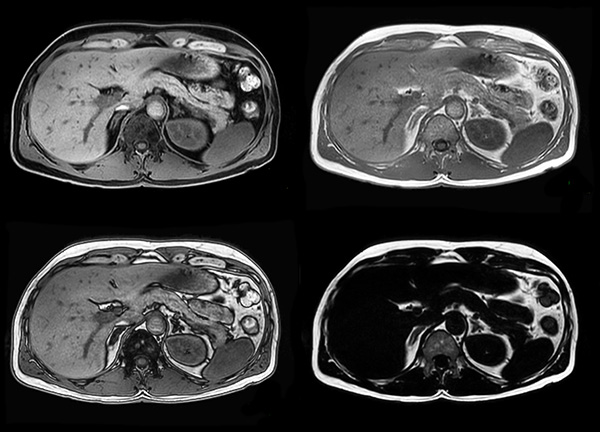

Axial mDIXON (W, IP, OP, F)